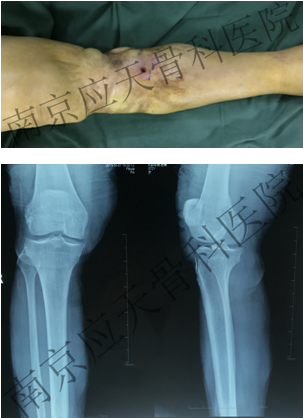

术前: